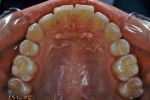

| 初診時